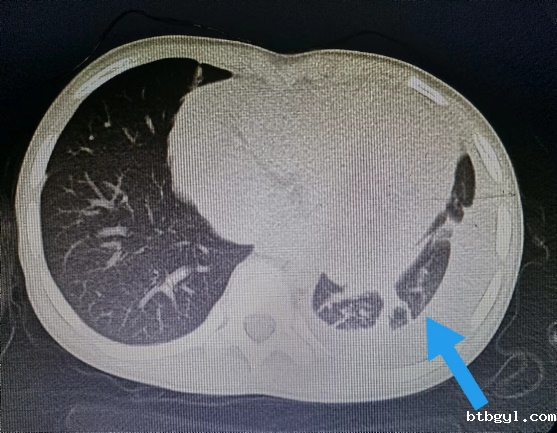

近日,一向身体健康的8岁的小男孩小阳(化名),几天前突然开始剧烈头痛,反复恶心、呕吐,奶奶赶紧把他送到我院就诊。 起初,大家认为小阳只是简单的感冒或则肠胃问题,普通检查没有找到病因,最终在颅脑CT提示下发现小阳“左侧枕叶脑出血伴血肿形成”。 患儿入院影像(左图为颅内出血、右图为胸腔积液及心包积液) 入住神经外科后,考虑到小阳近期并没有受过外伤,依据既往经验,小阳的脑出血可能是先天性血管畸形,但完善相关脑血管检查后却提示小孩脑血管正常,诊断一时陷入了僵局。 仔细问诊 查找蛛丝马迹 经过不断询问,副主任医师汪棋笙了解到小阳来自山区农村,且平时有喝生水和吃生螃蟹的习惯,汪棋笙似乎找到了诊断的关键。回顾了小阳血常规结果嗜酸性粒细胞较正常增高4倍,结合患儿心肺CT提示心包积液、胸腔积液,存在多器官损害表现,汪棋笙高度怀疑小阳就是肺吸虫感染、脑型肺吸虫病。 多方打探 从成都邀请工作人员上门检测 近年来肺吸虫病感染率非常低,肺吸虫血清抗体检测在周边各大医疗中心均已停止开展此项检查,诊断再次陷入困难。经多方打听,最终联系到可以开展此项检测的机构,为此,科室立即联系,邀请工作人员从成都赶来上门抽血检测。最终确立了肺吸虫感染、脑型肺吸虫病的诊断。 寻遍全省 获得特效药 尽管小阳的诊断已明确,可新的问题又再次出现,治疗肺吸虫的特效药物“吡喹酮片”医院及市场上已经无法购得。科室可谓是全员出动,寻遍各级医疗机构,最终从四川省疾控中心获得该药物,治愈了小阳。 患儿出院影像(颅内出血、胸腔积液及心包积液已基本吸收) 特别提醒: 饮用生水或吃了未经煮熟的青蛙、蛇等肉类,容易导致寄生虫感染,寄生虫可进入血管,并通过血液循环进入大脑内生存,引发相关脑病。 肺吸虫是什么? 肺吸虫又称并殖吸虫,是甲壳类哺乳动物的常见人兽共患寄生虫。当它们在组织中迁移时会引发嗜酸性反应,因此我们可以在化验单上看到嗜酸性粒细胞增多。肺吸虫感染人体后主要寄生于肺部,还可异位至脑部、腹部及皮下等部位,引起相应的器官组织病变。 哪些习惯容易招虫? 近年来发病率有所下降,但在部分人或因饮生水、生食或者半生食虾蟹的习惯,导致该病时有发生。 如何预防肺吸虫感染? 1.不要随意喝生水,尤其是河水、小溪水等。 2.切勿吃生的淡水螃蟹、小龙虾等,一定要煮熟。 3.避免食用未煮熟的其它淡水甲壳类动物或来自污染水源的淡水鱼类。 神经外科联系电话:0830-5216264